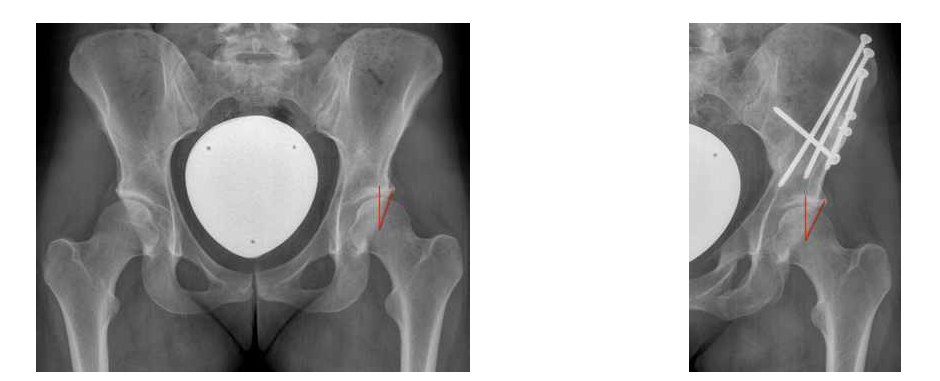

Die operative Therapie der Pfannendachdysplasie zielt auf eine Reduktion der Druck- und Scherbelastung des knöchernen und weichteiligen Pfannenrandes. Hierzu führen wir eine Dreifach-Beckenosteotomie (die sog. Triple-Osteotomie nach Tönnis und Kalchschmidt) durch, bei der die Hüftgelenkspfanne aus dem Beckenknochen durch drei „Knochenschnitte“ herausgelöst, in eine biomechanisch günstigere Position gedreht und in dieser mit Schrauben fixiert wird. Dieser Eingriff zieht eine verbesserte Hüftkopfüberdachung nach sich.